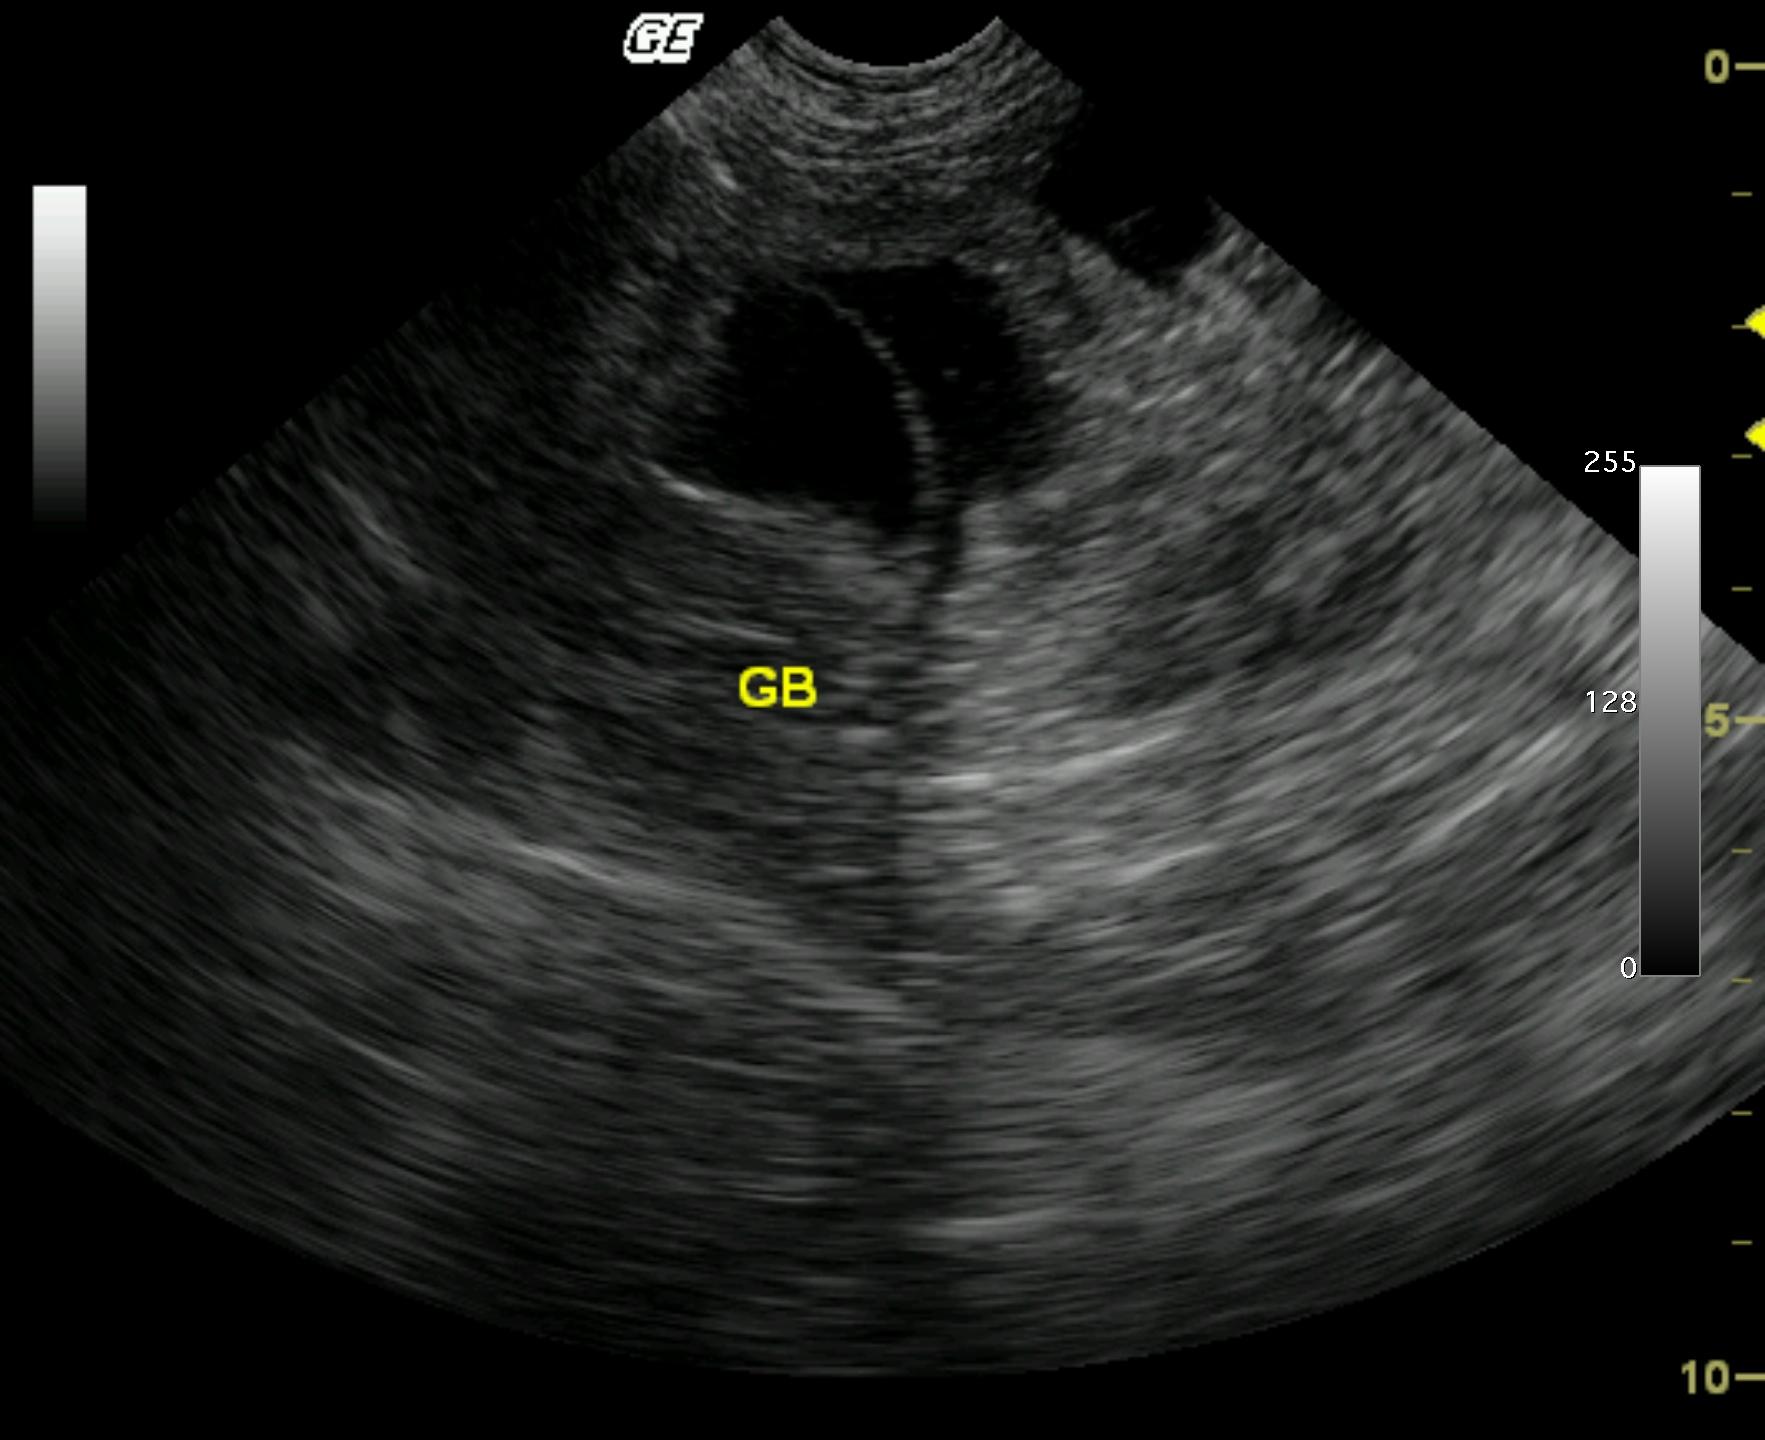

An 8-year-old MN DLH cat was presented with a 3-day history of lethargy, vomiting, and diarrhea. A palpable abdominal mass was present on physical examination. The initial blood chemistry profile revealed severely elevated ALT and severely elevated AST with moderate azotemia and a mildly elevated creatinine concentration. Urinalysis revealed a specific gravity of 1.059 and hematuria. Moderate non-regenerative anemia also was evident.